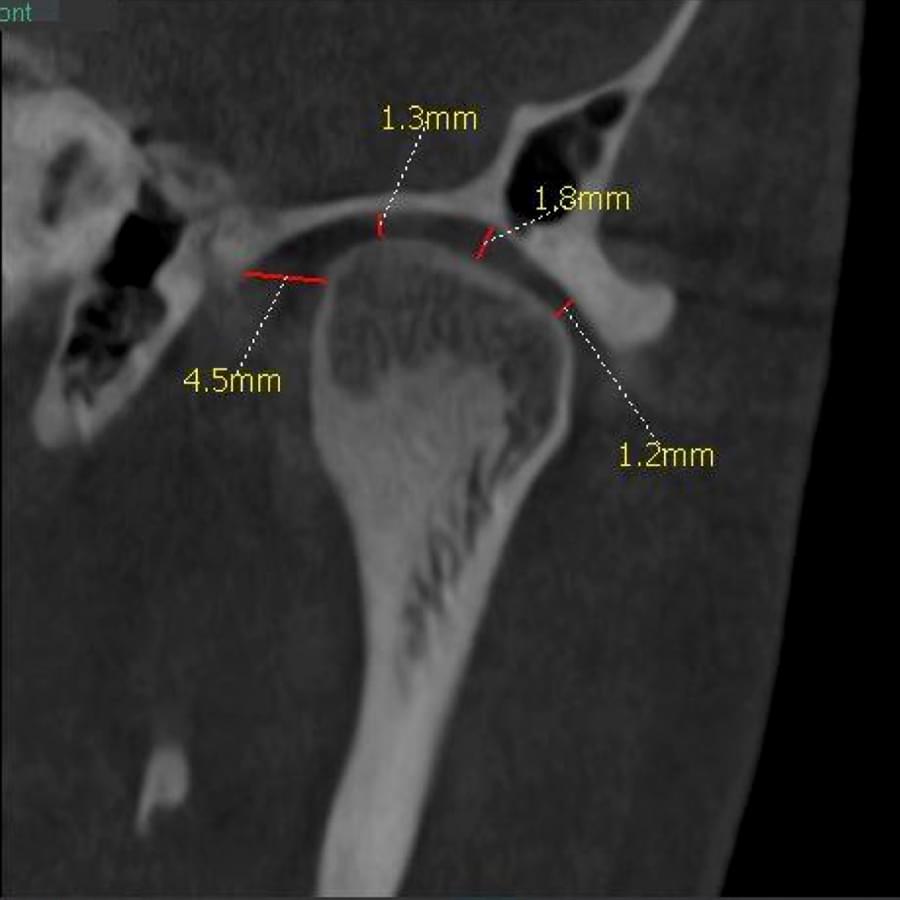

3D цефалометричний аналіз є сучасною технологією, яка дозволяє отримувати точніші,

комплексніші та надійніші дані про зубну та скелетну структуру. Ця технологія може стати

великим кроком в перед для ортодонтів, які хочуть забезпечити найкраще можливе лікування

своїх пацієнтів.

Основні переваги 3D цефалометричного аналізу:

Точність: 3D цефалометричний аналіз забезпечує точніше визначення розмірів та відстаней між

зубами та кістковими структурами.

Комплексність: ця технологія дозволяє отримувати детальні дані про різні структури, такі як

кістка та м'язи, що дозволяє ортодонтам докладніше досліджувати деякі патології та планувати

лікування.